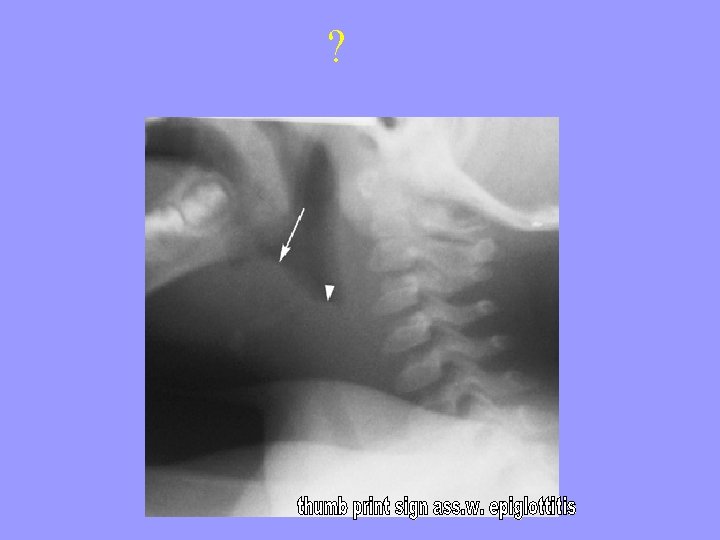

Epiglottitis - 2 Swallowing Drooling Barking cough No Toxicity Fever X-ray WBC count Severely toxic > 38. 5 C Thumb sign of thickened epiglottis High Neutrophil count Treatment Entotracheal Intubation involve senior Anaesthetist/ ENT Consultant. IV antibiotic Prevention None